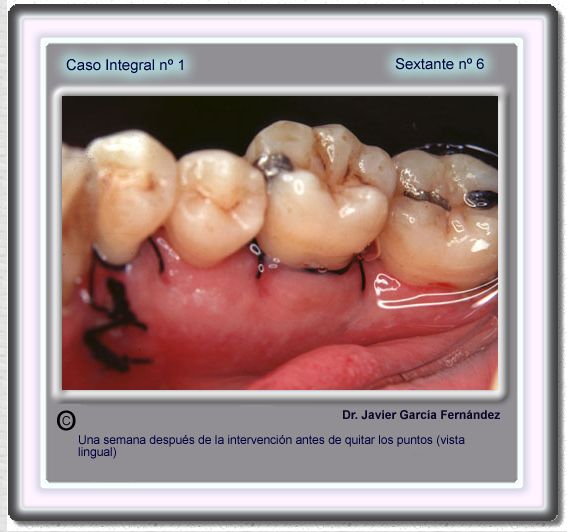

image 111